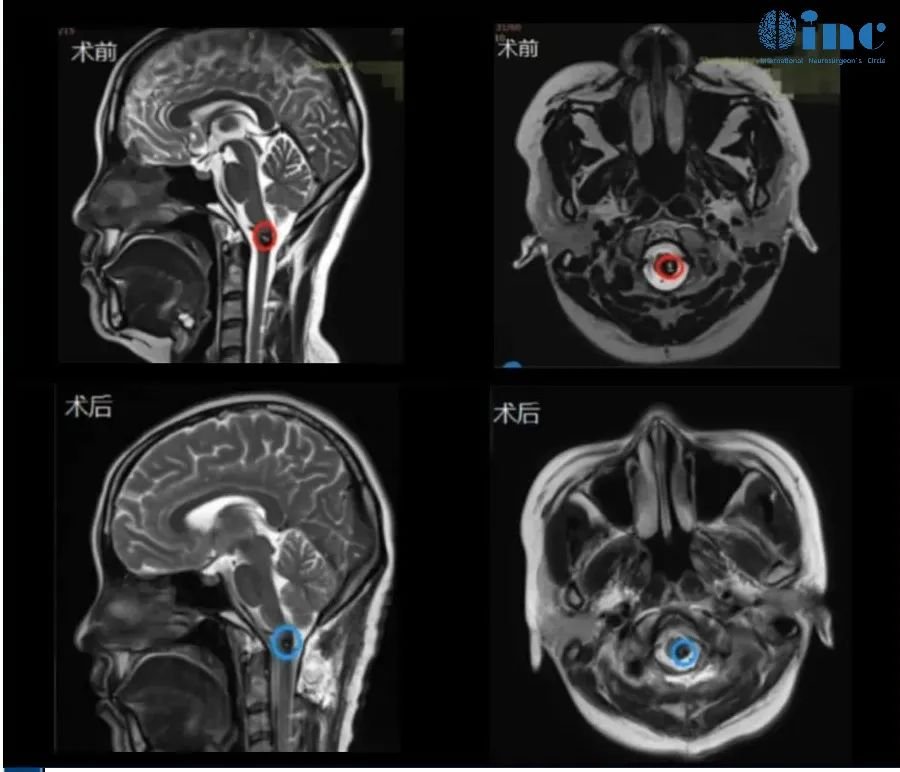

33岁女性-脑干颈髓室管膜瘤

14岁男孩-脑干神经节细胞胶质瘤

34岁男性-脑干延髓-颈髓室管膜瘤WHO2级

24岁男性-脑干延髓低级别胶质瘤

6岁男孩-延髓毛细胞星形细胞瘤

5岁女孩脊髓-脑干毛细胞星形细胞瘤